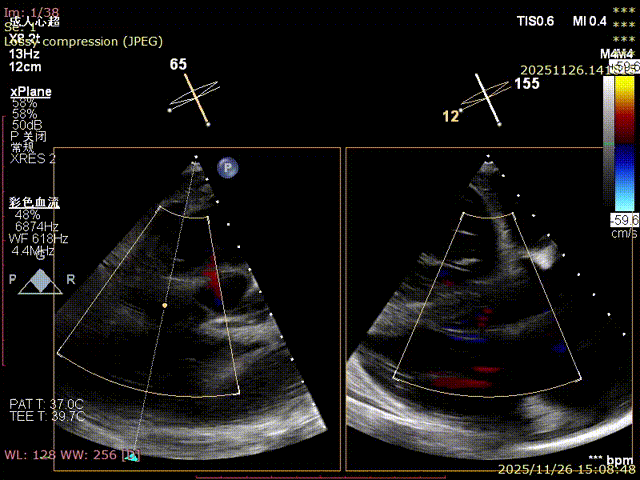

Echocardiography Findings: Severe tricuspid regurgitation (4+), with regurgitation jets primarily located at the postero-septal and central regions. The tricuspid annulus is dilated (annulus diameter: 42 mm).

Preoperative

Regurgitation: 4+

Postoperative

Mild regurgitation (1+)